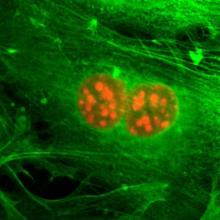

Detecting cancer is not always easy. Samples (biopsies) have to be studied under a microscope for signs of cancer. To make it easier to tell normal cells from cancer, dyes are used to color different parts of cells and tissues different colors.

That could be about to change. A new, hybrid,… more